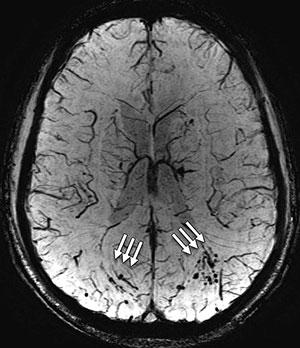

The MRI scans revealed the presence of white matter T2 hyperintensities, which can be thought of as brain scars, in 52 percent of the MTBI patients.

"We were really surprised to see so much damage to the brain in the MTBI patients," Dr. Riedy said. "It's expected that people with MTBI should have normal MRI results, yet more than 50 percent had these abnormalities."